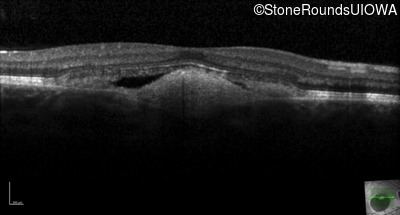

Visit at age: 18 years

Optical Coherence Tomography - Left - 20/30 -1 sc

Exemplar / OCT Stack

OCT Stack